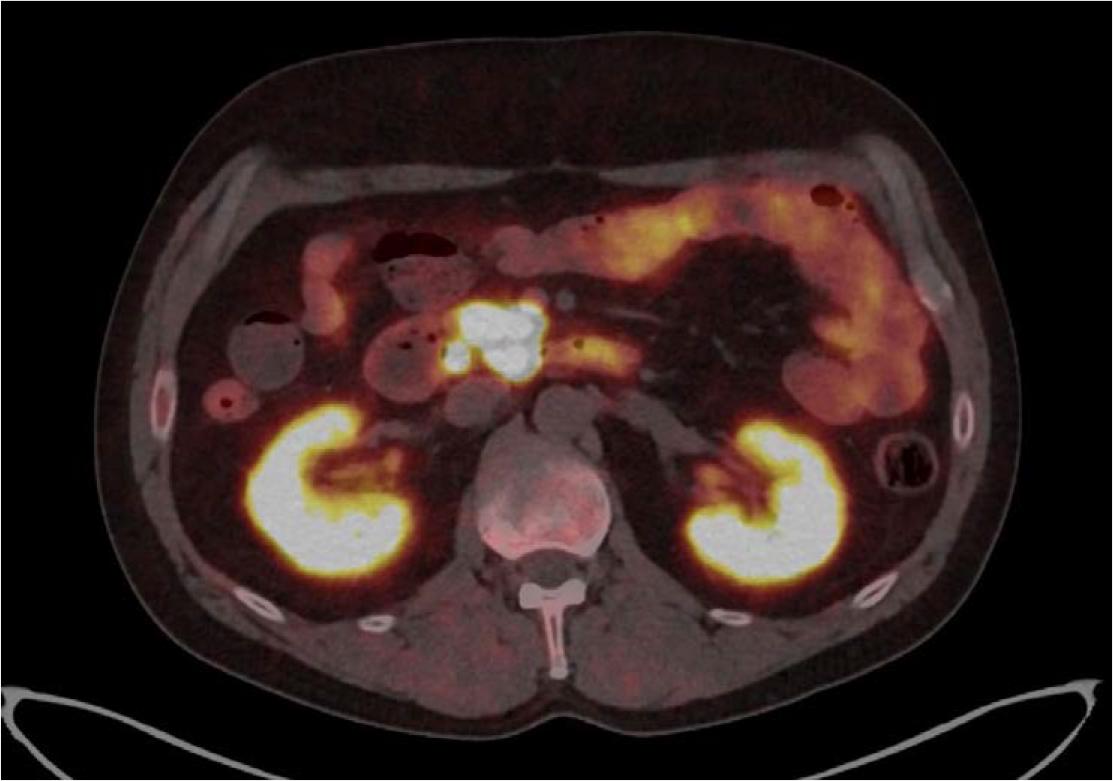

[68Ga]Ga-DOTA-TATE PET/CT, axial plane-Fused PET/CT axial image showing increased somatostatin receptor expression in a well-defined lesion localized between the duodenum and the uncinate process of the pancreas, later confirmed as a neuroendocrine neoplasm. Additional focal uptake is visible in regional lymph nodes, suggesting possible metastases.

Additionally, multiple enlarged lymph nodes were observed between the pancreatic head and duodenum and near the inferior mesenteric artery. These were all described as potential metastases.